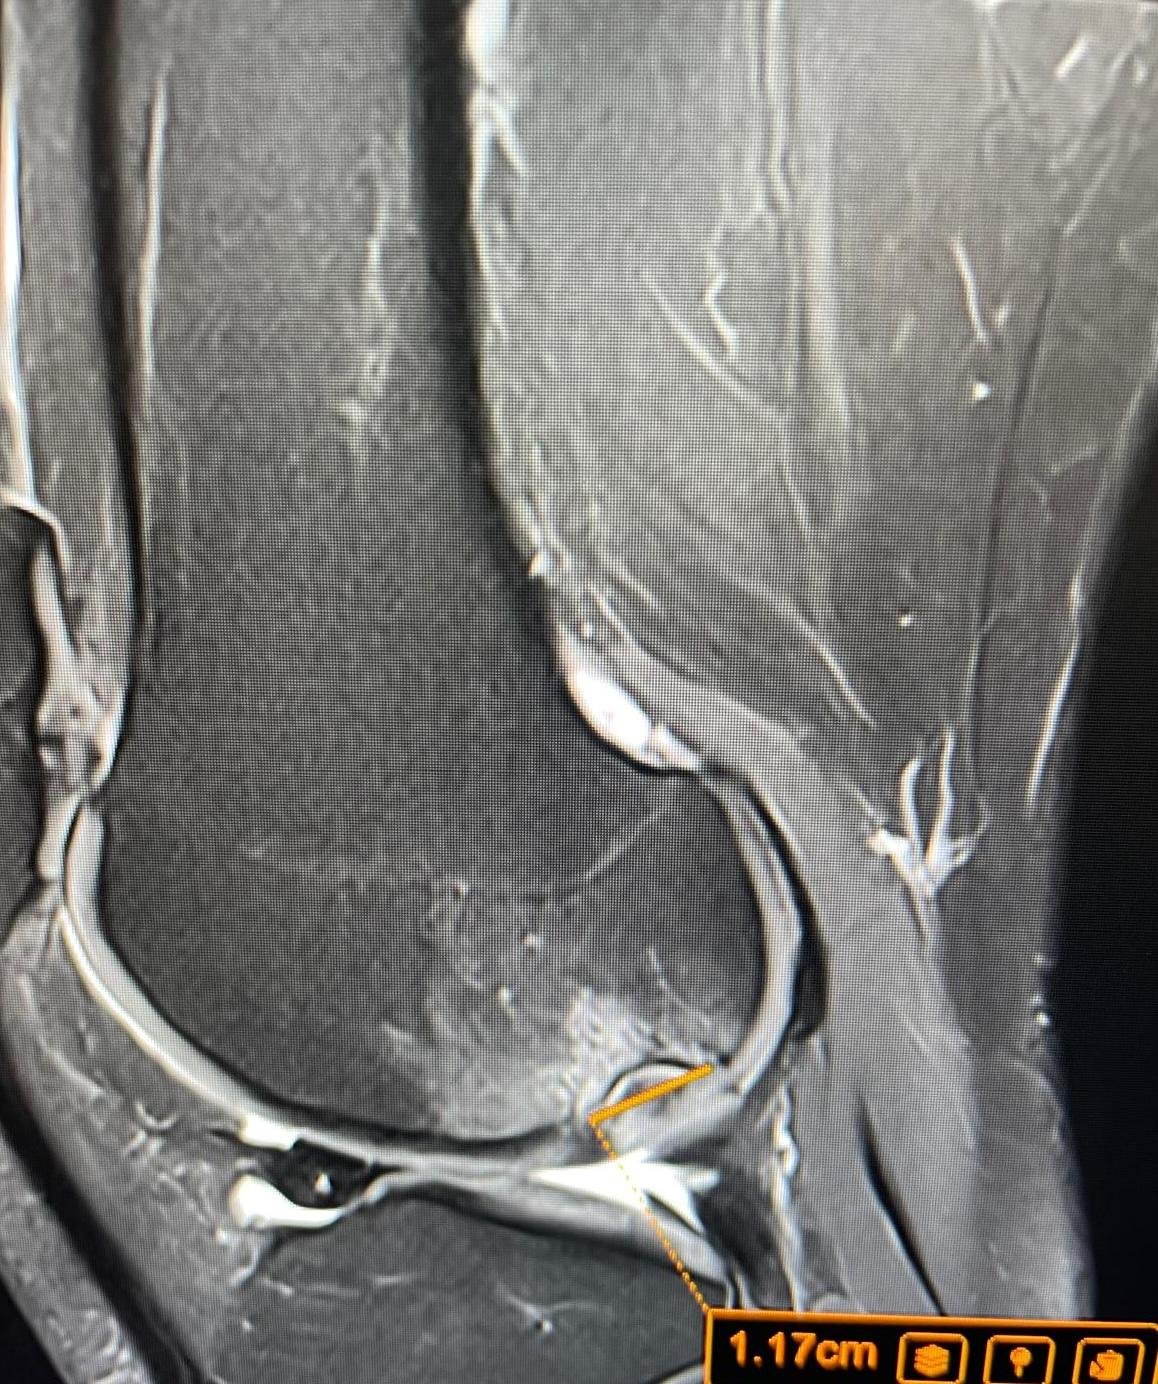

Knee, shoulder, hip, spine and sports injuries are our speciality. MSK MRI requires specialist expertise to interpret correctly. Your scan is read by a consultant with dedicated MSK radiology experience — not a generalist reporter.

Musculoskeletal imaging is a specialist field. Subtle findings — a partial rotator cuff tear, early cartilage loss, a stress reaction before it becomes a fracture — require dedicated expertise to identify and grade correctly.

• Knee — meniscus, ACL, cartilage